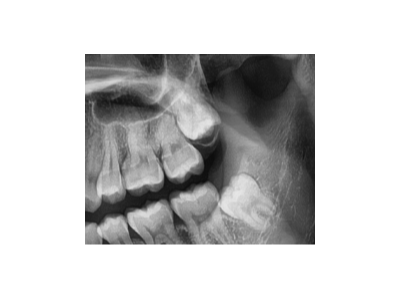

承德醫(yī)院洗牙結(jié)石多少錢一次

河北惟德口腔醫(yī)院告訴大家多數(shù)的成年人,經(jīng)常會(huì)發(fā)現(xiàn)自己牙齒內(nèi)側(cè)有牙結(jié)石、牙垢的情況,對(duì)于這類的牙齒問題其實(shí)是需要及時(shí)洗牙的,因?yàn)檫@些局部刺激會(huì)不斷的刺激牙齦,對(duì)于整體的口腔健康是非常不利的。對(duì)于洗牙結(jié)石…